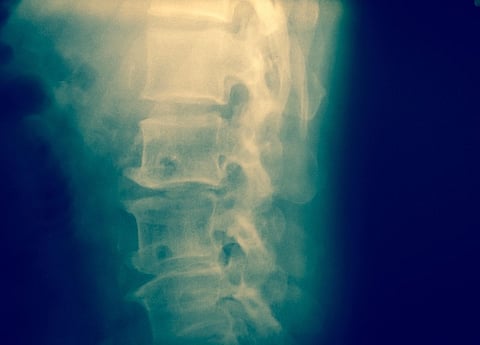

An experimental wraparound device can give a 360-degree view of the spinal cord

The device involves very thin, high-resolution implants wrapped around the entire spinal cord, providing for the first time a safe 360-degree view of the spine.

“Most technologies for monitoring or stimulating the spinal cord only interact with motor neurons along the back, or dorsal, part of the spinal cord,” said co-lead researcher Dr. Damiano Barone, a clinical lecturer in neursurgery at the University of Cambridge School of Clinical Medicine. “These approaches can only reach between 20% and 30% of the spine, so you’re getting an incomplete picture.”